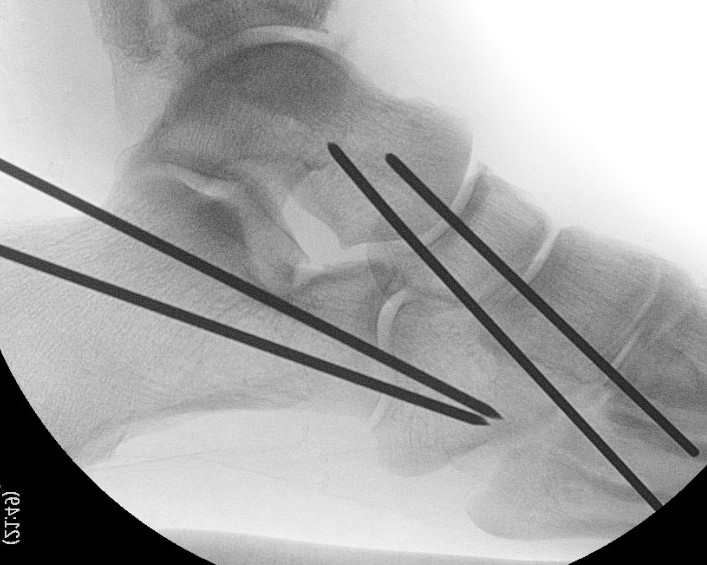

Pure ligamenous dislocation fixation

- percutaneous K wires

Urgent closed +/- reduction reduction

Anatomic reduction and stabilization

- dorsomedial - talonavicular joint

- dorsolateral approach - calcaneocuboid joint